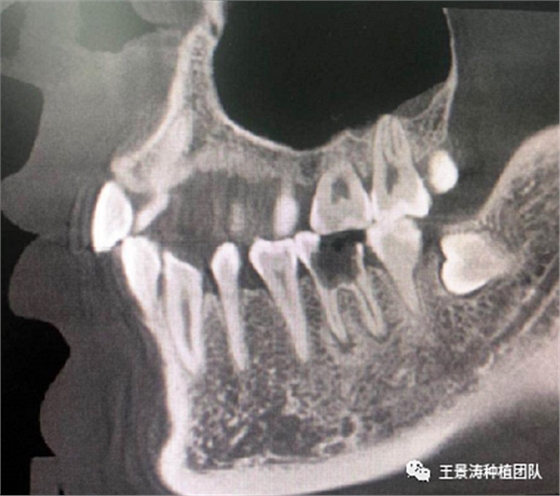

下述病例則是15區(qū)域的即刻種植,15因牙冠折斷于齦下,無法樁核冠修復(fù),則考慮種植修復(fù)。但拍攝CBCT后發(fā)現(xiàn)根尖距上頜竇底距離較短?;颊邽槟贻p女性,無全身系統(tǒng)疾病且可利用上頜竇底與根尖皮質(zhì)骨雙側(cè)皮質(zhì)骨固位,且此位置可通過頰側(cè)軟組織減張技術(shù)獲得嚴(yán)密封閉牙槽窩。因其根尖距上頜竇距離較低,遂拔除15后行上頜竇內(nèi)提升,埋入式種植,最終修復(fù)的完成。